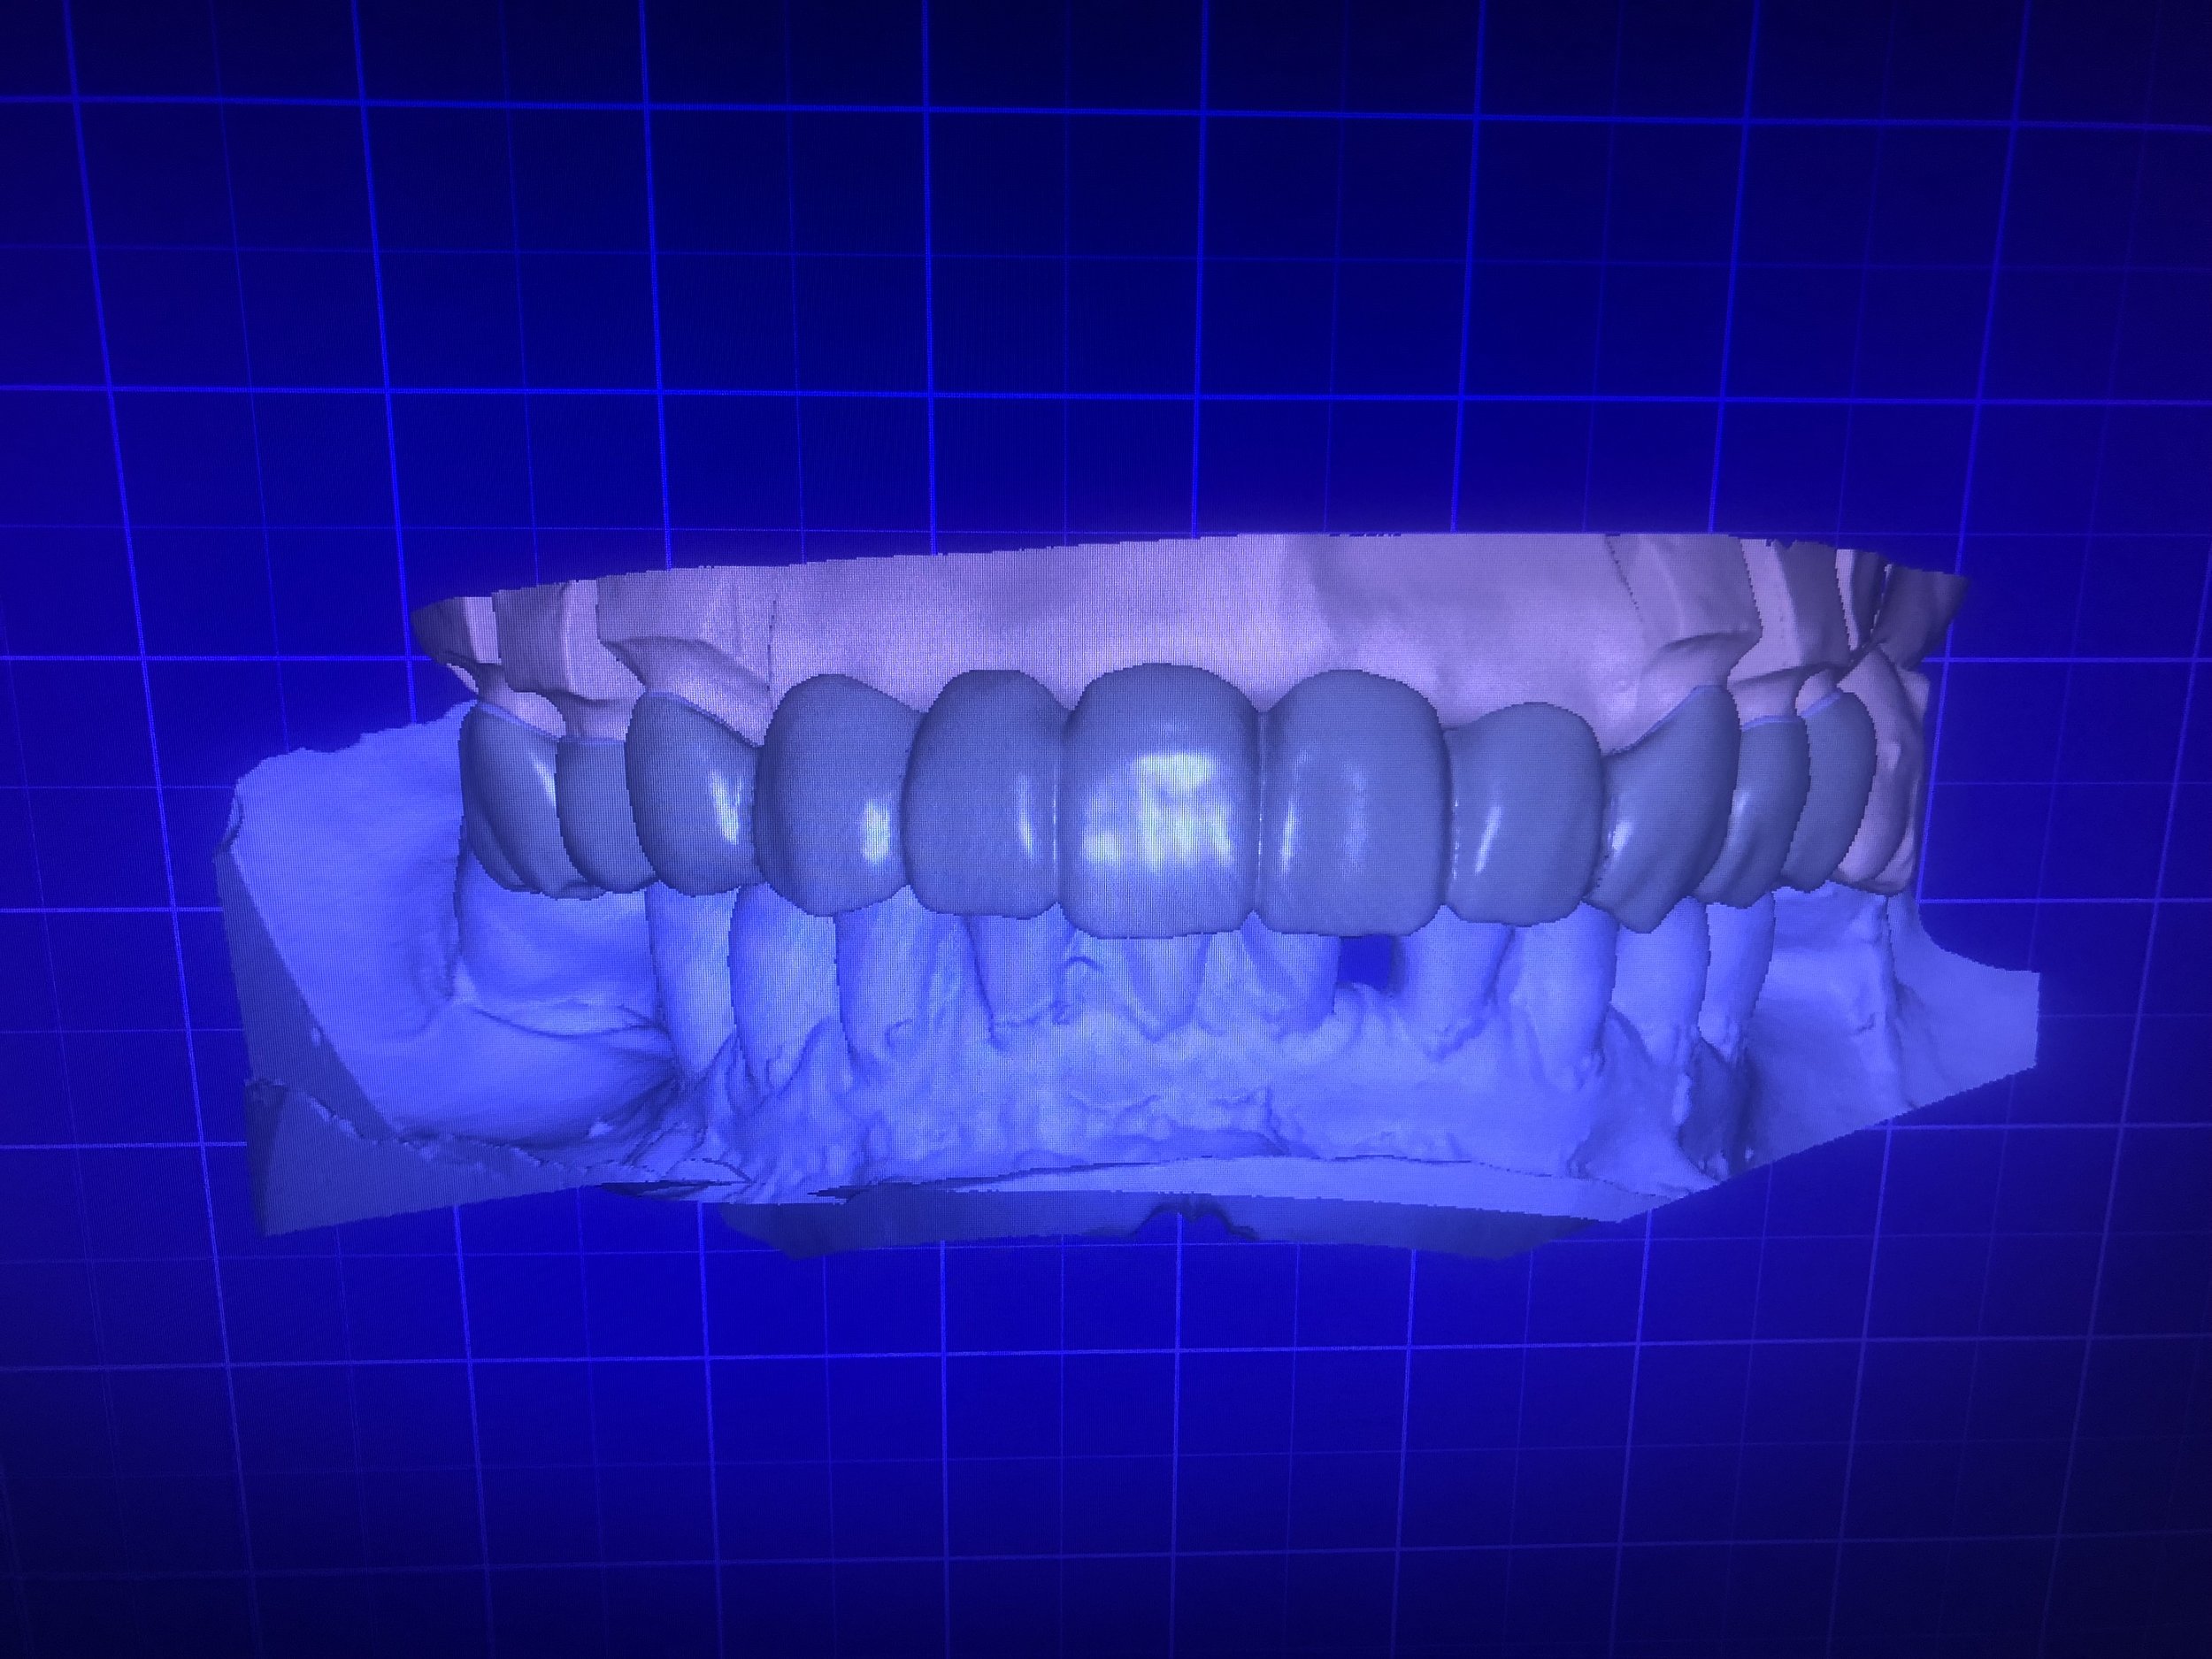

Advantages of Digital Dentistry

Superior Accuracy & Predictable Results

With precise 3D scans and CAD/CAM-designed prosthetics, treatments fit perfectly the first time—reducing remakes and speeding up patient care.